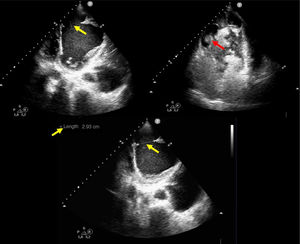

This is the case of a 61-year-old woman who had a myocardial infarction one month prior and subsequently developed post-infarction mechanical complications. The echocardiogram revealed the presence of a large apical pseudoaneurysm (Figs. 1 and 3: blue arrow) (Appendix A Video), with a 2.93cm neck (Figs. 1 and 2: yellow arrow) and free flow of echocontrast through it (Fig. 2: red arrow). The lumen was partially thrombosed (Figs. 1 and 3: white arrow). She also exhibited severe left ventricular dilatation and very severe global systolic dysfunction (Fig. 1) (LVEF 11%; LVOT VTI 7cm). Forty-eight hours after admission, the patient developed SCAI C-D cardiogenic shock, requiring mechanical support with V-A ECMO and an intra-aortic balloon pump, which led to a significant improvement in organ perfusion. After coordination with the referral hospital, she underwent a code 0 heart transplant, with a favorable recovery. This case highlights the importance of echocardiographic diagnosis and mechanical support management in critical situations of cardiogenic shock.